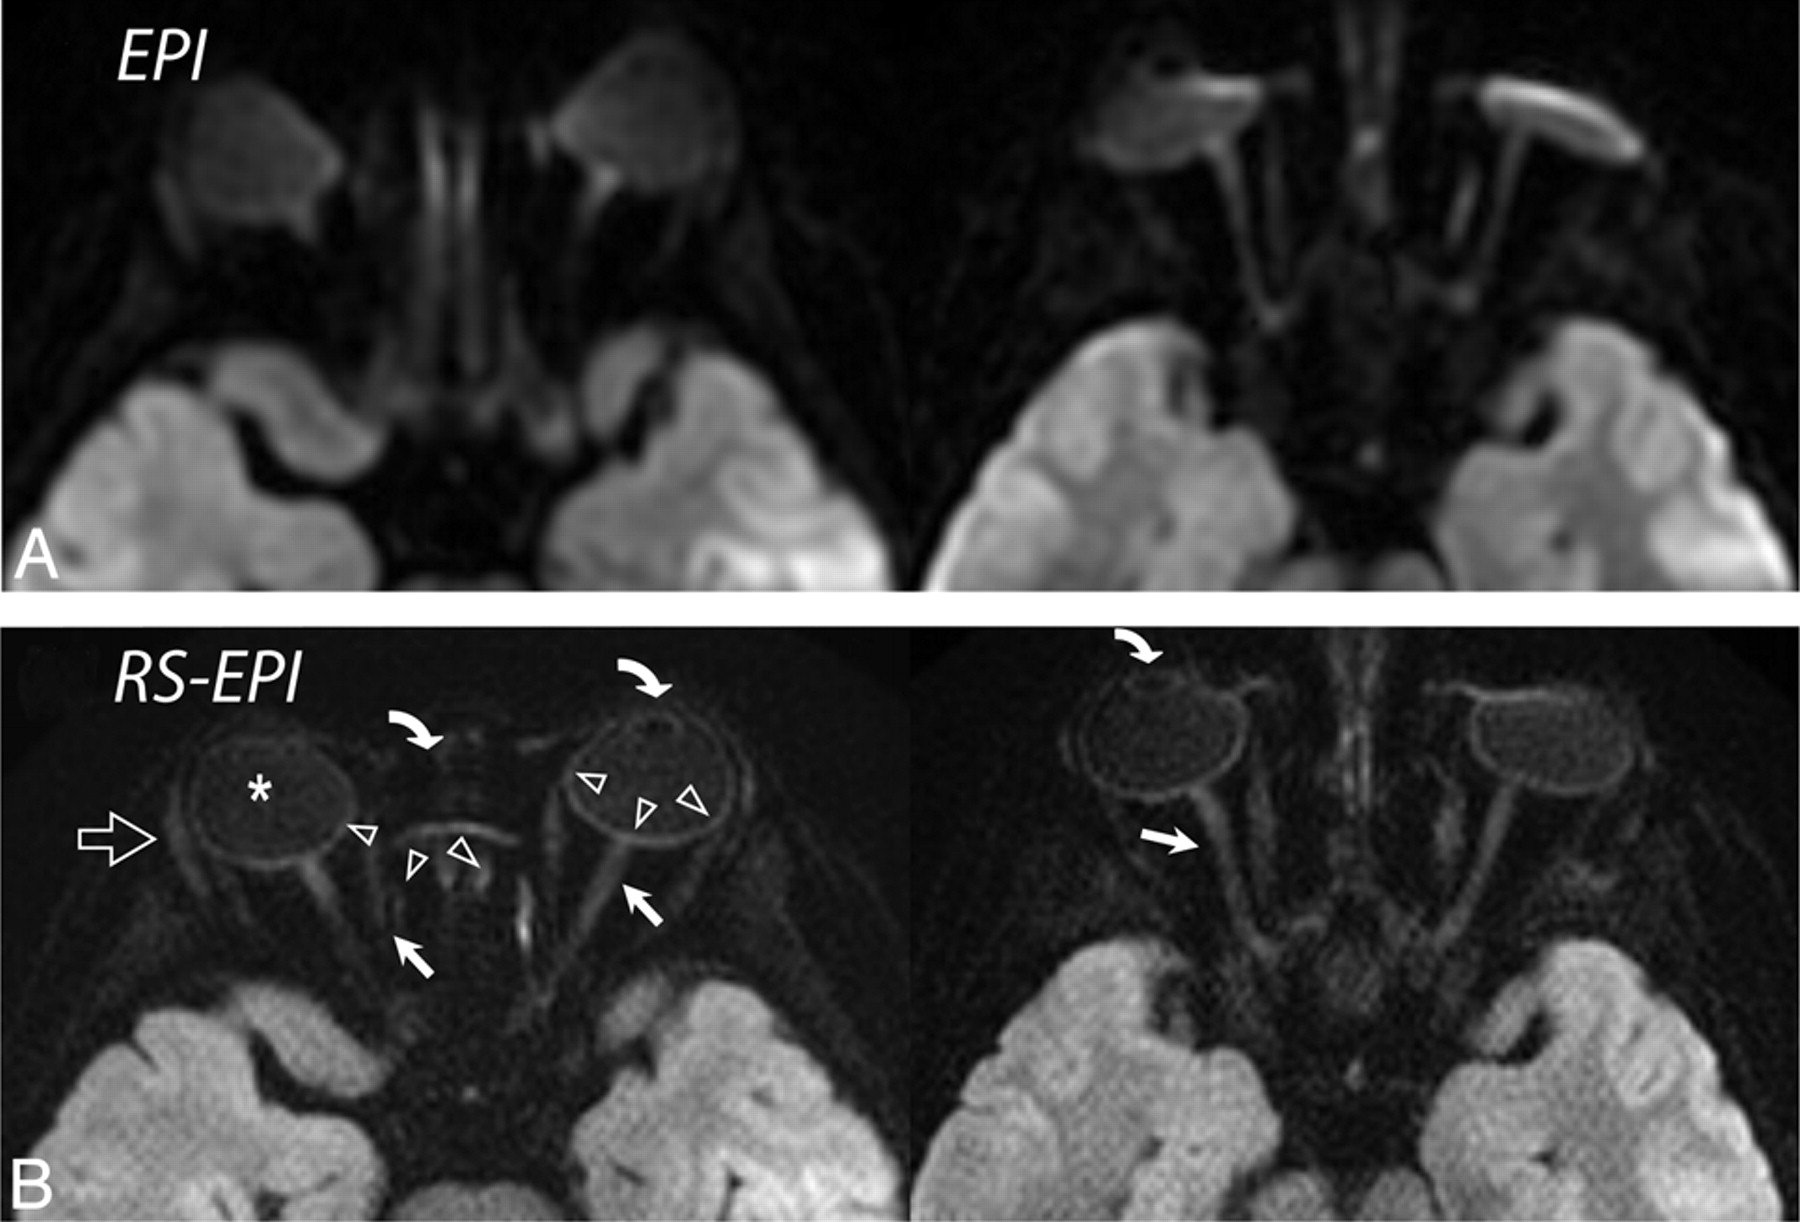

Although ASSET EPI scans had better SNR efficiency (ie, SNR per square root of the scanning time), the higher spatial resolution as well as reduced blurring and distortions on RS-EPI scans improved anatomic details at the cortical-subcortical levels, brain stem, temporal and inferior frontal lobes, skull base, nasoethmoid region in interior cranial fosa, the cranial nerves, and the orbits. Exquisite orbital detail was delineated in all 35 RS-EPI scans. Figure 9 shows side-by-side comparisons between ASSET EPI (top) and RS-EPI (bottom) DWIs in 2 patients and highlights these findings. Figure 9A shows a patient with a small subdural empyema in the middle cranial fossa, which was equivocal on conventional ASSET EPI, mostly because of poor resolution and profound signal intensity loss along the orbits. On RS-EPI, orbital details such as the optic nerve and medial rectus muscle were more clearly outlined compared with ASSET EPI. Also, due to less distortion, RS-EPI enabled tumor delineation more clearly, even at the anterior skull base and near air–soft tissue interfaces, such as the nasoethmoid. This illustrates a potential clinical use of RS-EPI in evaluating highly cellular pediatric tumors, such as neuroblastoma, retinoblastoma, and rhabdomyosarcoma, which have a propensity to occur in regions susceptible to distortion.

A, ASSET-accelerated (×2) diffusion-weighted single-shot EPI in 2 different subjects (a 3-year-old girl and a 10-year-old boy) and their corresponding diffusion-weighted RS-EPI scans. B, ASSET EPI scans have a better SNR, but orbital anatomy, such as the lens (curved arrows), optic nerve (arrows), sclera (arrowheads), vitreous humor (asterisk), and lacrimal glands (open arrow), are clearly better depicted on RS-EPI than on conventional ASSET-accelerated EPI scans.